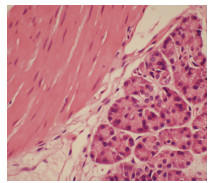

Effect of Shuganning injection on the model of cholestasis - type chlorpromazine - induced liver injury constructed by a new tissue - engineered liver

Abstract(1201) HTML (437) PDF (4120KB)(53)

Objective  To investigate the effect of Shuganning injection (SGN) in alleviating drug-induced cholestasis and the possible mechanisms involved.  Methods  The liver of Sprague-Dawley rats was decellularized to prepare collagen scaffolds, and then the scaffolds were recellularized with human HepG2 cells to obtain the tissue-engineered liver (normal control group). The tissue-engineered liver was perfused with 10 μmol/L chlorpromazine (CPZ) and bile salt mixture to establish a model of drug-induced cholestasis (CPZ group), and the model was further treated with Shuganning injection (103-fold dilution) as the injury protection group (SGN+CPZ group). The markers for hepatocellular injury [alanine aminotransferase (ALT), aspartate aminotransferase (AST), lactate dehydrogenase (LDH), and alkaline phosphatase (ALP)] and the antioxidant and oxidative stress markers [glutathione (GSH), malondialdehyde (MDA), superoxide dismutase (SOD), and reactive oxygen species (ROS)] were measured for all groups, and the normal control group, the CPZ group, and the SGN+CPZ group were compared in terms of the mRNA and protein expression levels of the enzymes associated with liver bile salt metabolism and the enzymes associated with hepatic cholestasis. HE staining was performed to observe liver pathology. A one-way analysis of variance was used for comparison of continuous data between multiple groups, and the least significant difference t-test was used for further comparison between two groups.  Results  Compared with the CPZ group, the SGN+CPZ group had significant reductions in the markers for hepatocellular injury ALT, AST, LDH, and ALP (all P < 0.000 1), significant increases in the oxidative stress markers GSH and SOD (P < 0.000 1 and P < 0.001), and significant reductions in the markers MDA and ROS (P < 0.000 1 and P < 0.001). Compared with the CPZ group, the SGN+CPZ group had significant reductions in the mRNA expression levels of cholesterol 7α-hydroxylase (CYP7A1) and sterol 12α-hydroxylase (CPY8B1) in hepatocytes (all P < 0.001) and significant increases in the mRNA expression levels of farnesoid X receptor (FXR), small heterodimeric partner (SHP), bile salt export pump (BSEP), and multidrug resistance-associated protein 2 (MRP2) (P < 0.000 1, P < 0.01, P < 0.000 1, and P < 0.000 1). HE staining showed that compared with the CPZ group, the SGN+CPZ group had a significant reduction in hepatocyte injury and a significant increase in the number of cells.  Conclusion  Shuganning injection can alleviate drug-induced cholestatic liver injury caused by chlorpromazine, and it exerts a protective effect by activating FXR in hepatocytes and increasing the expression of SHP to regulate bile salt balance. It also inhibits CYP7A1 and CYP8B1 to reduce the synthesis of hydrophobic bile acids and upregulates the expression of BSEP and MRP2 to promote the excretion of bile salts.